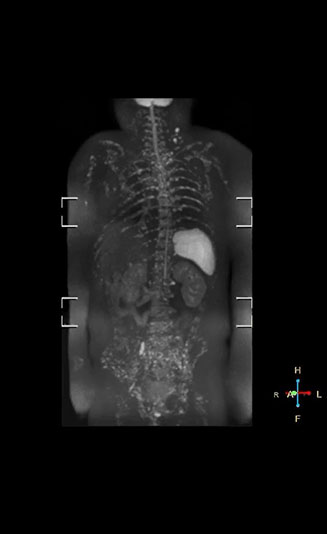

Recognizing the clinical utility of whole body MR imaging, radiologists at Kawasaki Saiwai Hospital (Kasawaki, Japan) began offering whole body diffusion weighted imaging (DWI) in 2009 for oncology patients. In 2012, the hospital installed a Philips scanner, the Ingenia 1.5T. The dStream digital architecture and highly linear gradients of Ingenia allowed them to switch to coronal – rather than axial – whole body DWI, and were key to developing a fast, high quality protocol that has led to increased referrals and decreased dependence on nuclear medicine imaging.

“Switching to coronal DWIBS – rather than axial – further shortens scan time,” says Mr. Naka. “Important is that a dS SENSE factor of 5 shortens exam time while high image quality can be maintained, thanks to Ingenia’s dStream architecture.” He adds that the coronal orientation also avoids artifacts that are specific to combining axial images.

“When we use a coronal DWIBS acquisition, we can perform a full whole body examination, including other required sequences, within 30 minutes,” he says.